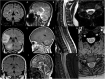

Relapsing demyelinating syndromes (RDS) in children encompass a diverse spectrum of entities including multiple sclerosis (MS) acute disseminated encephalomyelitis (ADEM), aquaporin-4 antibody associated neuromyelitis optica spectrum disorder (AQP4-NMOSD) and myelin oligodendrocyte glycoprotein antibody disease (MOG-AD). In addition to these, there are "antibody-negative" demyelinating syndromes which are yet to be fully characterized and defined. The paucity of specific biomarkers and overlap in clinical presentations makes the distinction between these disease entities difficult at initial presentation and, as such, there is a heavy reliance on magnetic resonance imaging (MRI) findings to satisfy the criteria for treatment initiation and optimization. Misdiagnosis is not uncommon and is usually related to the inaccurate application of criteria or failure to identify potential clinical and radiological mimics. It is also notable that there are instances where AQP4 and MOG antibody testing may be falsely negative during initial clinical episodes, further complicating the issue. This article illustrates the typical clinico-radiological phenotypes associated with the known pediatric RDS at presentation and describes the neuroimaging mimics of these using a pattern-based approach in the brain, optic nerves, and spinal cord. Practical guidance on key distinguishing features in the form of clinical and radiological red flags are incorporated. A subsection on clinical mimics with characteristic imaging patterns that assist in establishing alternative diagnoses is also included.